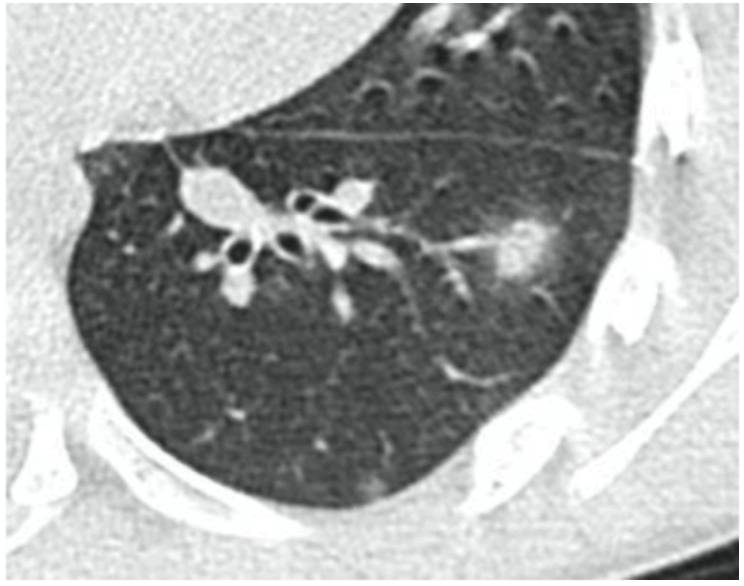

ы матового стекла